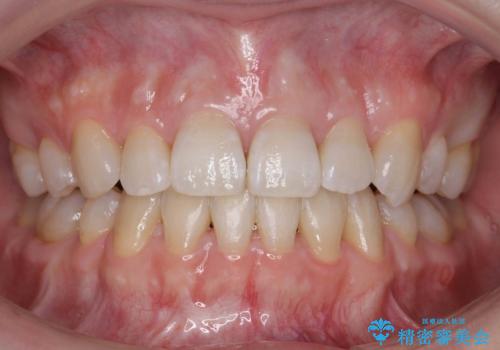

治療期間はかかりましたが、右下4が一生もつとは思えない状態でしたので、人工物を入れないようにすることができました。

矯正治療をしない場合は、右下はブリッジかインプラントが必要になっていたと思います。

上顎前歯も唇側傾斜しておらず、もともと叢生が多くない状態で上下左右を抜歯した上、リンガルで治療を行なったため、多少治療期間がかかりました。